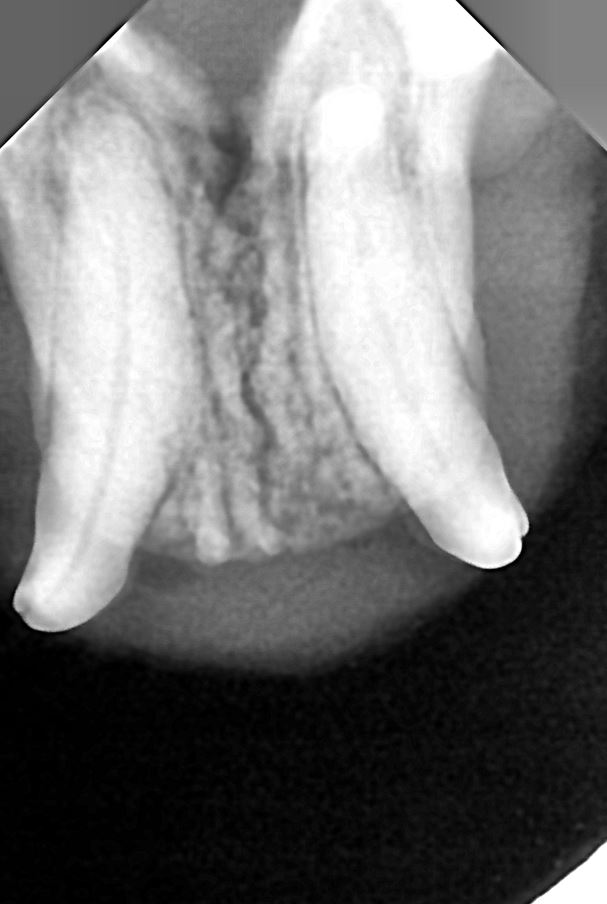

| 치료과정 | 꼬리는 상태가 조금 나아졌다싶으면 사라졌다가 매우 악화된 모습으로 나타나기를 반복하고는 했다 더이상 약도 큰 효과가 없었고 피섞인 침을 흘리며 음식물을 먹지 못하며 점점 상황이 심각해져가서 전발치및 입원치료가 필요성을 느끼고 치료지원신청을 하게 되었다. 어느 날 갑자기 사라져서 걱정했는데 다행히 다시 나타나서 구조하게 되었다. 치료지원신청 당시 미리 신청해두었던 동물병원으로 이송했는데, 선생님께서 꼬리는 당장 전발치를 감당할수 있는 체력이 아니라고 하였다. 조금이라도 더 나은 체력상태를 만들기 위해 꼬리는 얼마간 수액을 맞고 체력보충을 하고나서 전발치를 하게되었다. 여태까지는 유석 동물병원에서 전발치 수술+목구멍레이저를 함꼐하는 치료프로토콜이었는데, 이번에는 목구멍레이저는 실시하지 않는 곳이어서 그런건지,아니면 꼬리의 상태가 오랫동안 (1년이상으로 추측) 너무 심각해서 그런건지 전발치를 하고나서, 충분한 입원치료를 하고나서도 침을 흘리는 증상이 지속되었고 방사를 할 수 있는 건강상태로 쉽게 회복되지 못했다. *엑스레이 사진은 동물병원에서 주신 전발치 방사선과 전발치 이후 케어 과정. |